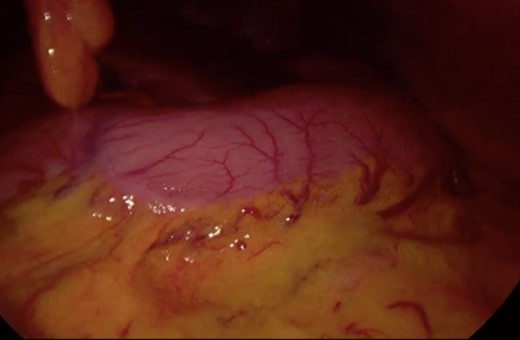

Initially, conservative management was adopted with some improvement of patient’s nutrition condition. However, as symptoms persisted, surgical treatment was recommended. Our surgical approach was a laparoscopic duodenojejunostomy with a latero-lateral stapled anastomosis between jejunum (30 cm from Treitz’s angle) and the second portion of the duodenum (Figs 5–9). The patient recovered with no pain but with a delay in diet acceptance. An upper GI contrast study was performed on the fifth post-operative day revealing a distended stomach with gastric emptying delay, but with unobstructed anastomosis, therefore without stenosis or leaks (Fig. 10). She was discharged home after 8 days with liquid diet and digestive transit restored. After 3 months of follow-up, the patient gained some weight and remained asymptomatic.

Surgery—initial laparoscopic view with distended stomach and proximal portions of duodenum.